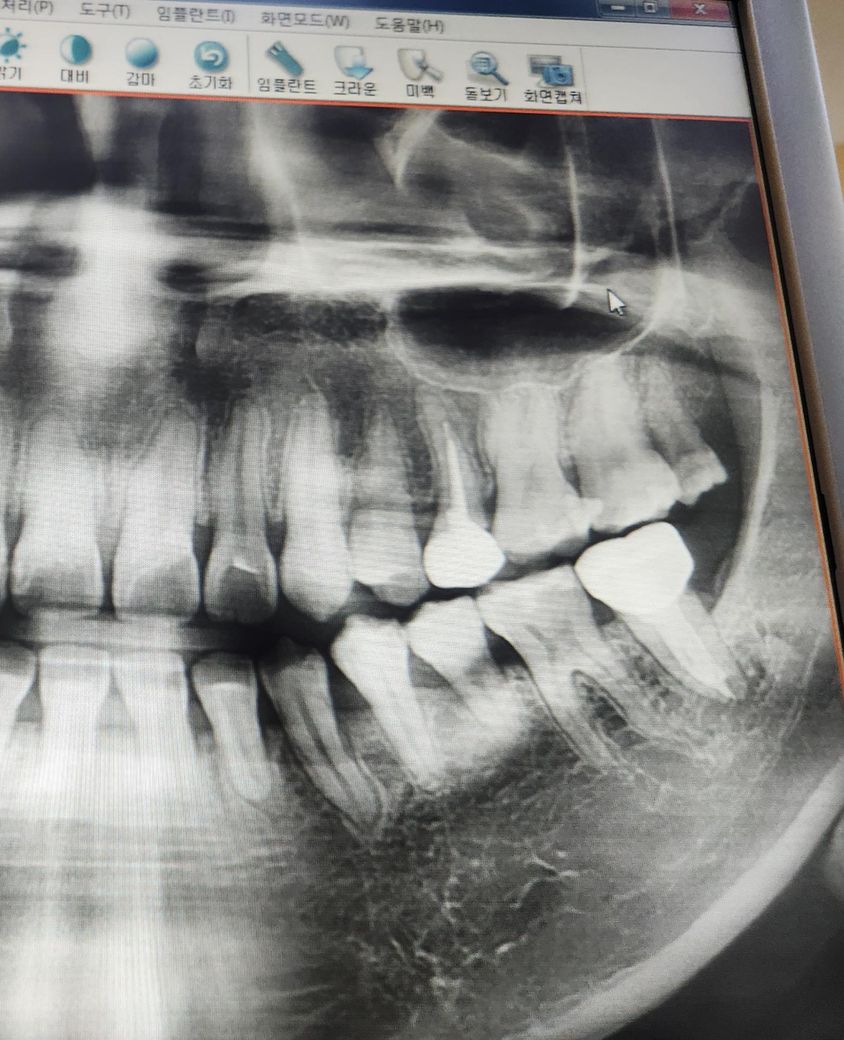

2년전에 충치로 인해 신경치료+크라운을 윗니에 진행하였는데습니다

그런데 1달전부터 크라운 씌운 치아를 누르거나 만지면 감각이 있기 시작했습니다

신경치료 전처럼 찬바람이나 찬물 뜨거운물에 통증을 느끼거나 시리진않고 크라운부위를 손으로 살짝 밀거나 손톱으로 두드리면 욱신하면서 시린느낌이 들고, 간혹 차가운 음료수를 먹게되면 시린느낌이 듭니다(찬물에는 감각이 없습니다)

이러한 증상으로 3주에전에 치과 두곳에서 검진을 받고, ct를 찍었는데 선생님들은 다 괜찮다고 하십니다

1.첨부한 ct사진에서 문제가 되는곳이 있나요?

2.보기에는 충치가 있는부위나 크라운 한곳에 염증이 있나요?

• 1번 째 사진

1. 해당사진은 ct가 아니고 파노라마 엑스레이입니다 자세히보려면 ct를 찍어보세요

2. 염증이 있어보이진 않습니다

3. 놓친 신경관이 있거나 사용된 포스트의 식립 각도나 두께가 이상적이지 않아 그럴 수도 있습니다